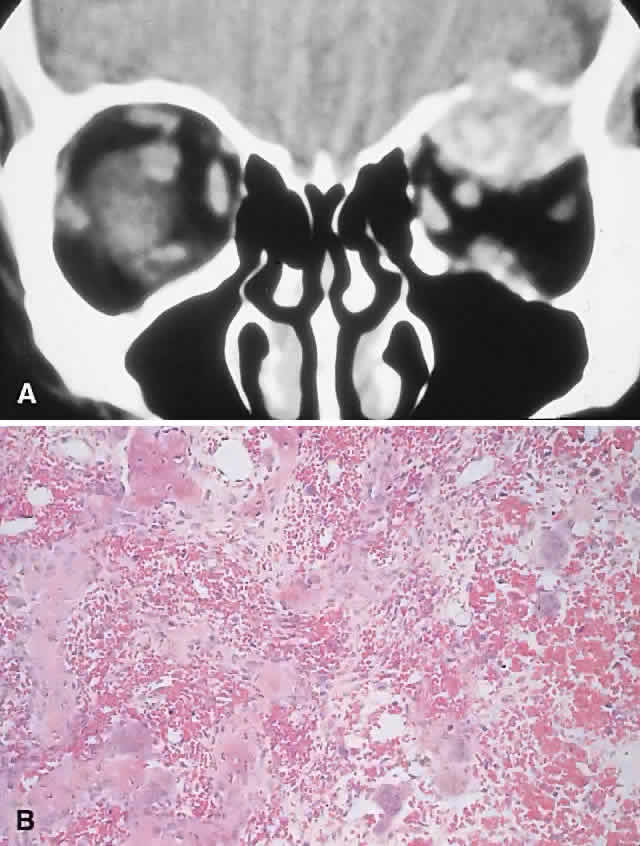

PRESENTATION. Proptosis and ocular displacement are the most common presentations, although headache and pain may be prominent (Fig. 7). Diplopia and decreased vision also occur, depending on the site of the mass. The time course is variable, ranging from months to years, and may be complicated by a rapid progression of symptoms resulting from hemorrhage.

Fig. 7. A 22-year-old man experienced left proptosis over several weeks. A. On examination, he had 7 mm of proptosis with 3 mm of lateral and inferior globe displacement. B and C. CT revealed a heterogeneous superior orbital mass with destruction of the roof, leading to extradural extension. D. A frontal craniotomy was performed, and histology showed a giant cell granuloma with a fibrous stroma containing plump fibroblasts and giant cells (hematoxylin-eosin, × 50). There was no recurrence at follow-up 4 years later. (B from Rootman J: Diseases of the Orbit: A Multidisciplinary Approach, p 369. Philadelphia: JB Lippincott, 1988.)

IMAGING. GCG typically manifests as a destructive lesion with erosion of adjacent bone. It may have indistinct or sclerotic margins and may show moderate enhancement of an often-inhomogeneous central matrix.

HISTOPATHOLOGY. Macroscopically, the granuloma consists of soft, friable, tan to brown tissue, typically in the form of curettings. A fibrous stroma with giant cells clustered around foci of hemorrhage is the dominant histology. This stroma contains ovoid and spindle-shaped fibroblasts with a variable amount of fibrosis and evidence of old and new hemorrhage. Reactive bone formation is common (75%) and consists of trabeculae of woven and lamellar bone, which may or may not demonstrate osteoblastic rimming. Areas of secondary aneurysmal bone cyst formation may also be seen.91,92,95